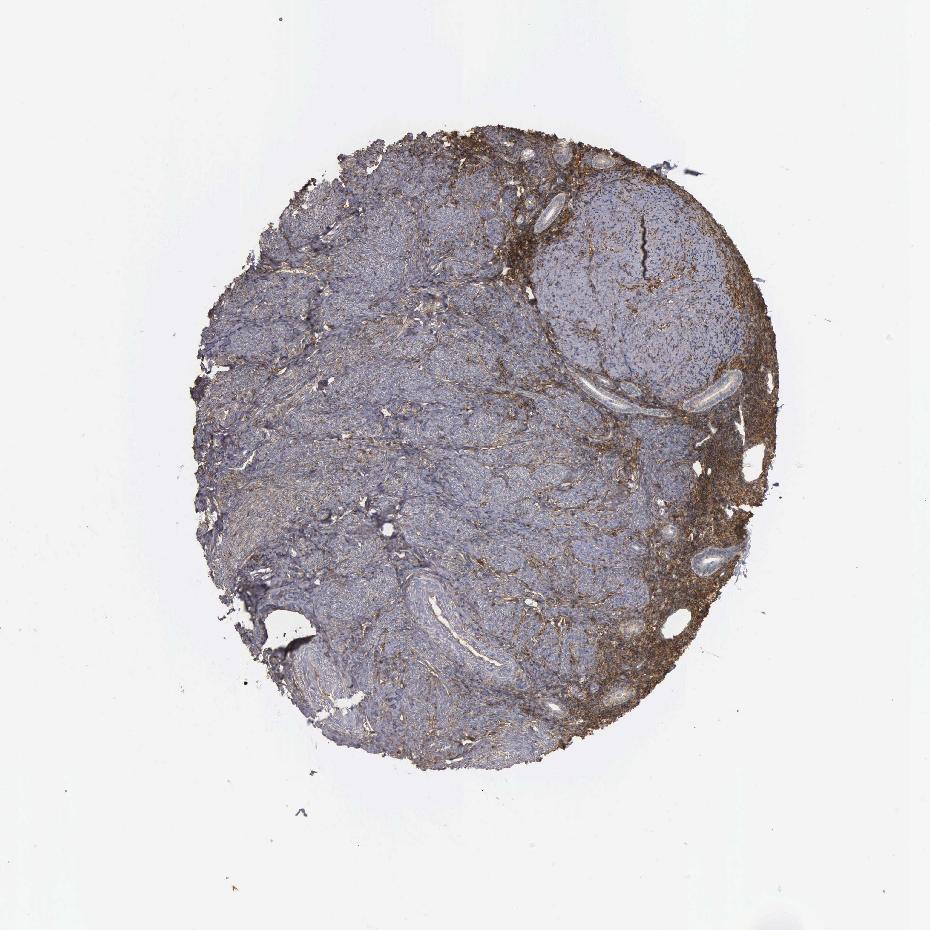

ENDOMETRIUM 1 - Antibody stainingi

Antibody staining in the annotated cell types in the current human tissue is reported as not detected, low, medium, or high, based on conventional immunohistochemistry profiling in selected tissues. This score is based on the combination of the staining intensity and fraction of stained cells.

Each image is clickable and will lead to virtual microscopy that enables deeper exploration of all samples and also displays staining intensity scores, fraction scores and subcellular localization as well as patient and tissue information for each sample.

Antibody HPA035304Antibody CAB000020

Cells in endometrial stroma Not detectedHigh

Glandular cells MediumLow

ENDOMETRIUM 2 - Antibody stainingi

Glandular cells MediumNot detected